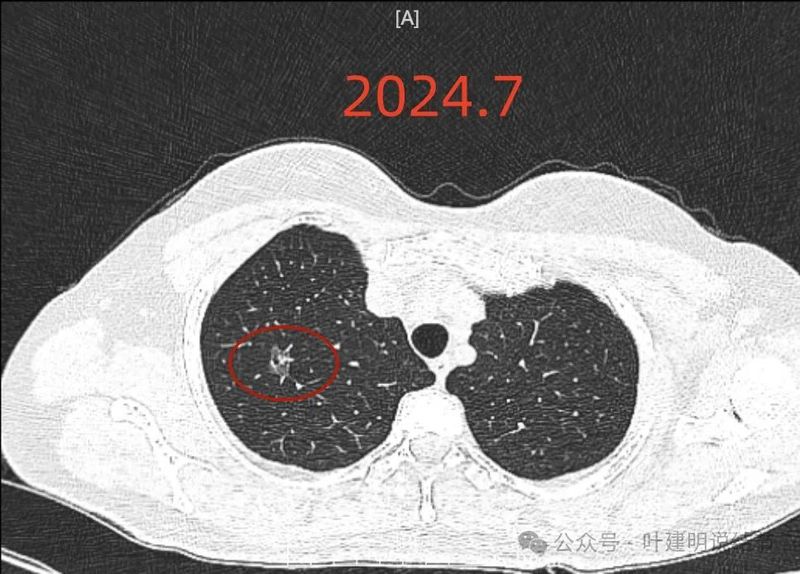

2024年7月时此灶已经在,而且密度不纯,整体轮廓与边界清。当时就是典型恶性的影像表现。

2024年9月病灶仍在,实性成分较前略显明显,矢状位清楚显示穿行血管壁毛糙。冠状位显示分叶以及病灶与血管间没有间隙。